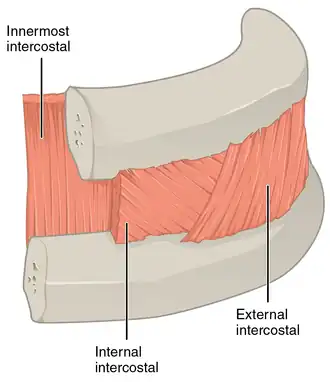

A cutout of the thoracic wall showing the three layers of intercostal muscle - from the left wall.

A cutout of the thoracic wall showing the three layers of intercostal muscle - from the left wall.